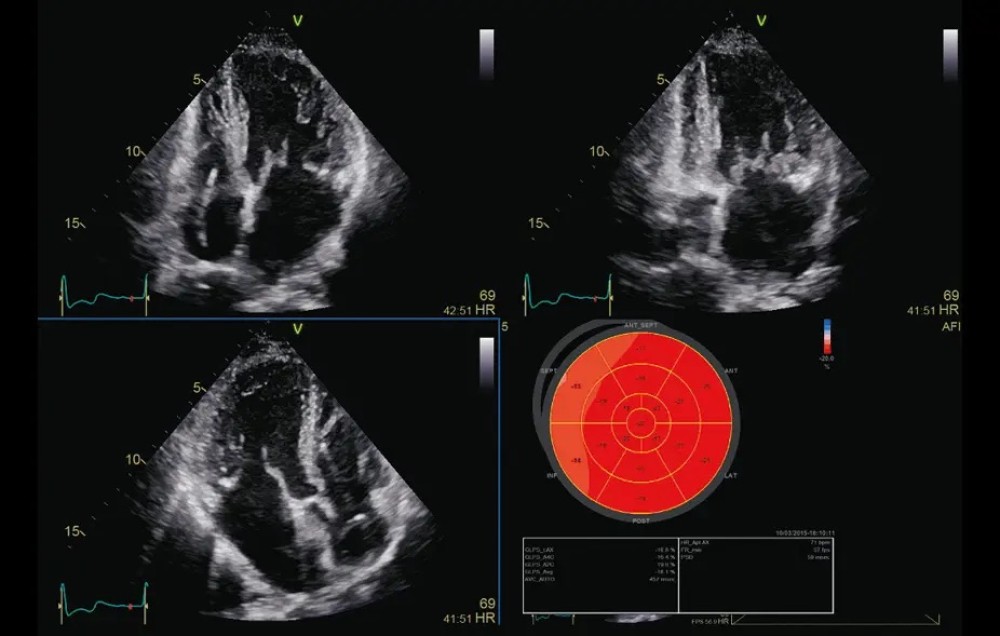

AFI (Automated Function Imaging) – avtomatik funksional görüntüləmə

AFI Stress – stress ekokardioqrafiya üçün avtomatik funksional görüntüləmə